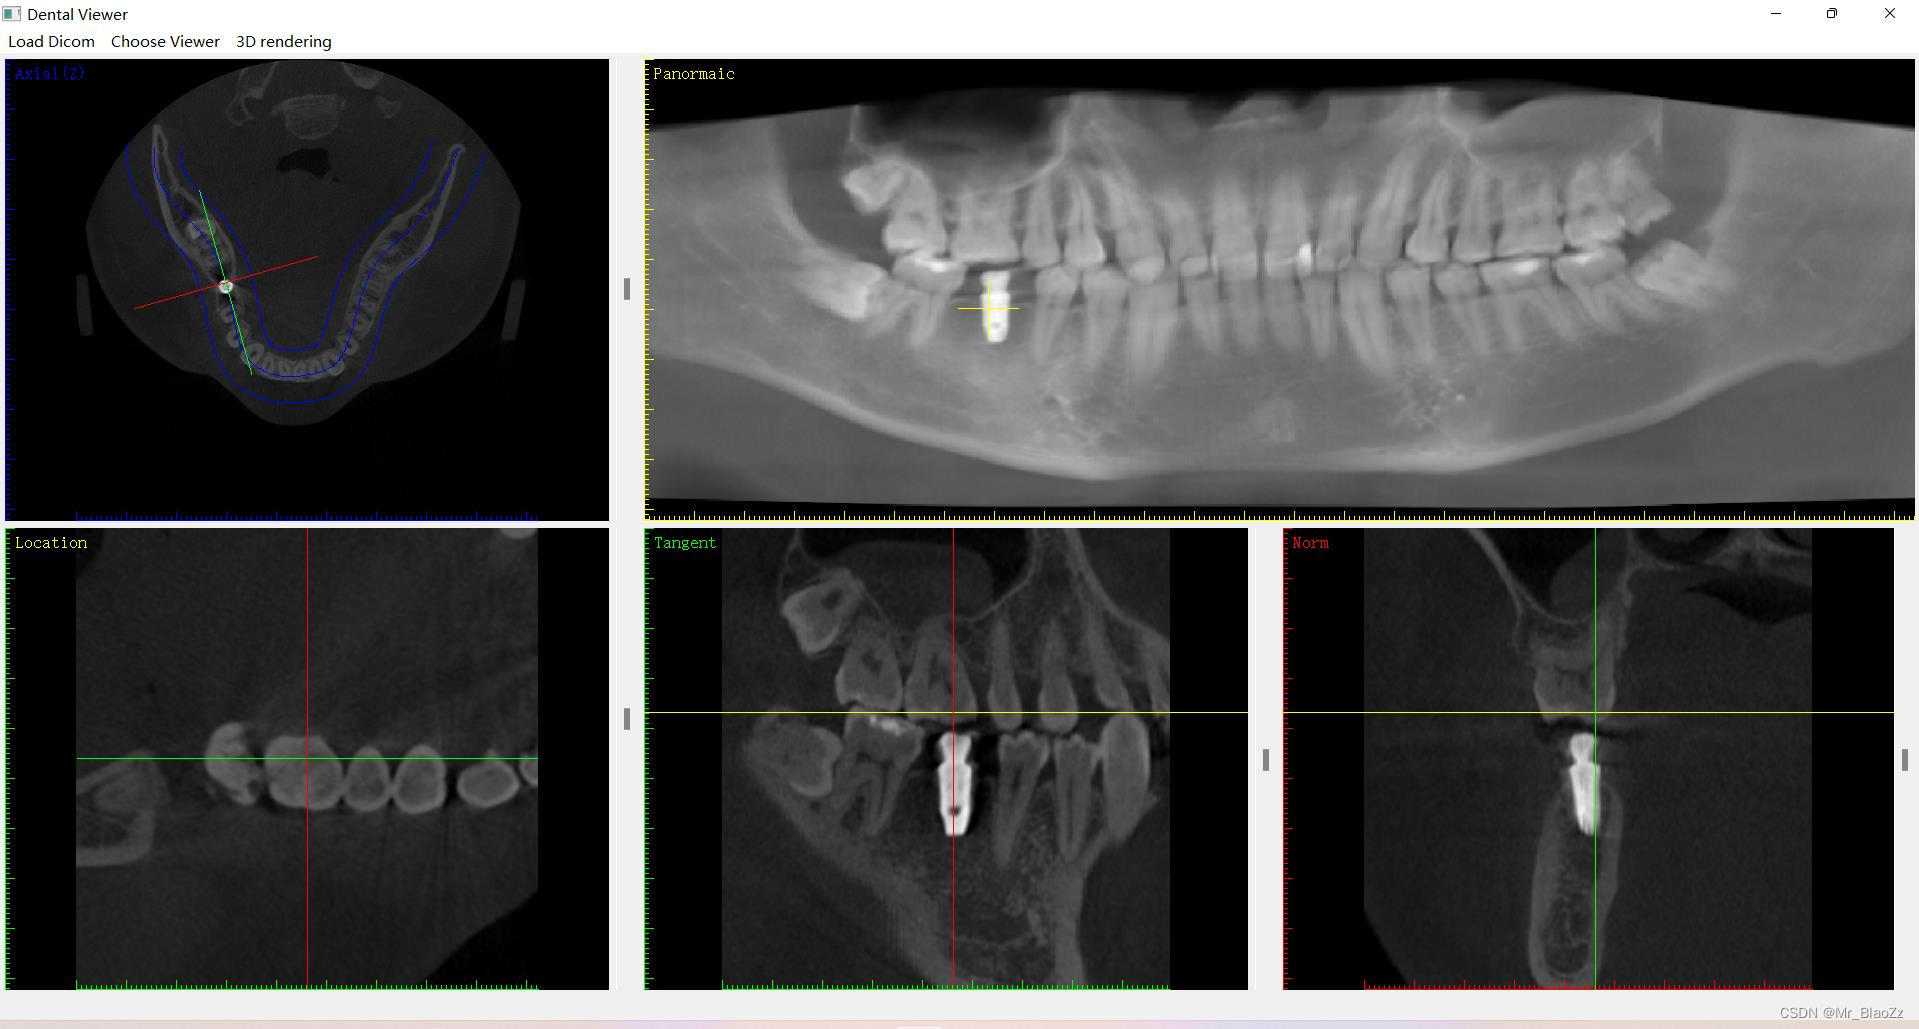

这次仿照一个软件的布局,实现了这款软件的大部分功能,功能大致差不多,主要使得整个界面布局以及内容更加完善,主要包含三个界面:三维视图、全景视图、种植视图。同时,也稍微了解下vtk库,实现了三维重建,基本了解了vtk的坐标系原理、坐标值、vtk空间中的各种绘制等等,但这些代码还没有完全整理出来。测试了三维模型的实时更新占用内存较多。后续会逐渐向vtk三维空间和界面交互方面完善。

ps:对于之前有些人一直问关于这个界面的部分,其实把CT数据当成一个长方体,用三把刀从上下、前后、左右三个方向去切这个长方体,然后三个面交于长方体内一点,就可以很好理解MPR图像了。另外,这里所有一个界面内所有视图都是联动的!由于本人未还未毕业暂不公布源码,有兴趣的可以评论交流就行。

仿造软件布局实现大部分功能,包括三维、全景和种植视图。初步掌握vtk库进行三维重建,理解坐标系原理。注意到三维模型实时更新内存消耗大,计划改进交互与界面。CT数据解释MPR图像原理,所有视图联动,未公开源码,欢迎交流。

仿造软件布局实现大部分功能,包括三维、全景和种植视图。初步掌握vtk库进行三维重建,理解坐标系原理。注意到三维模型实时更新内存消耗大,计划改进交互与界面。CT数据解释MPR图像原理,所有视图联动,未公开源码,欢迎交流。